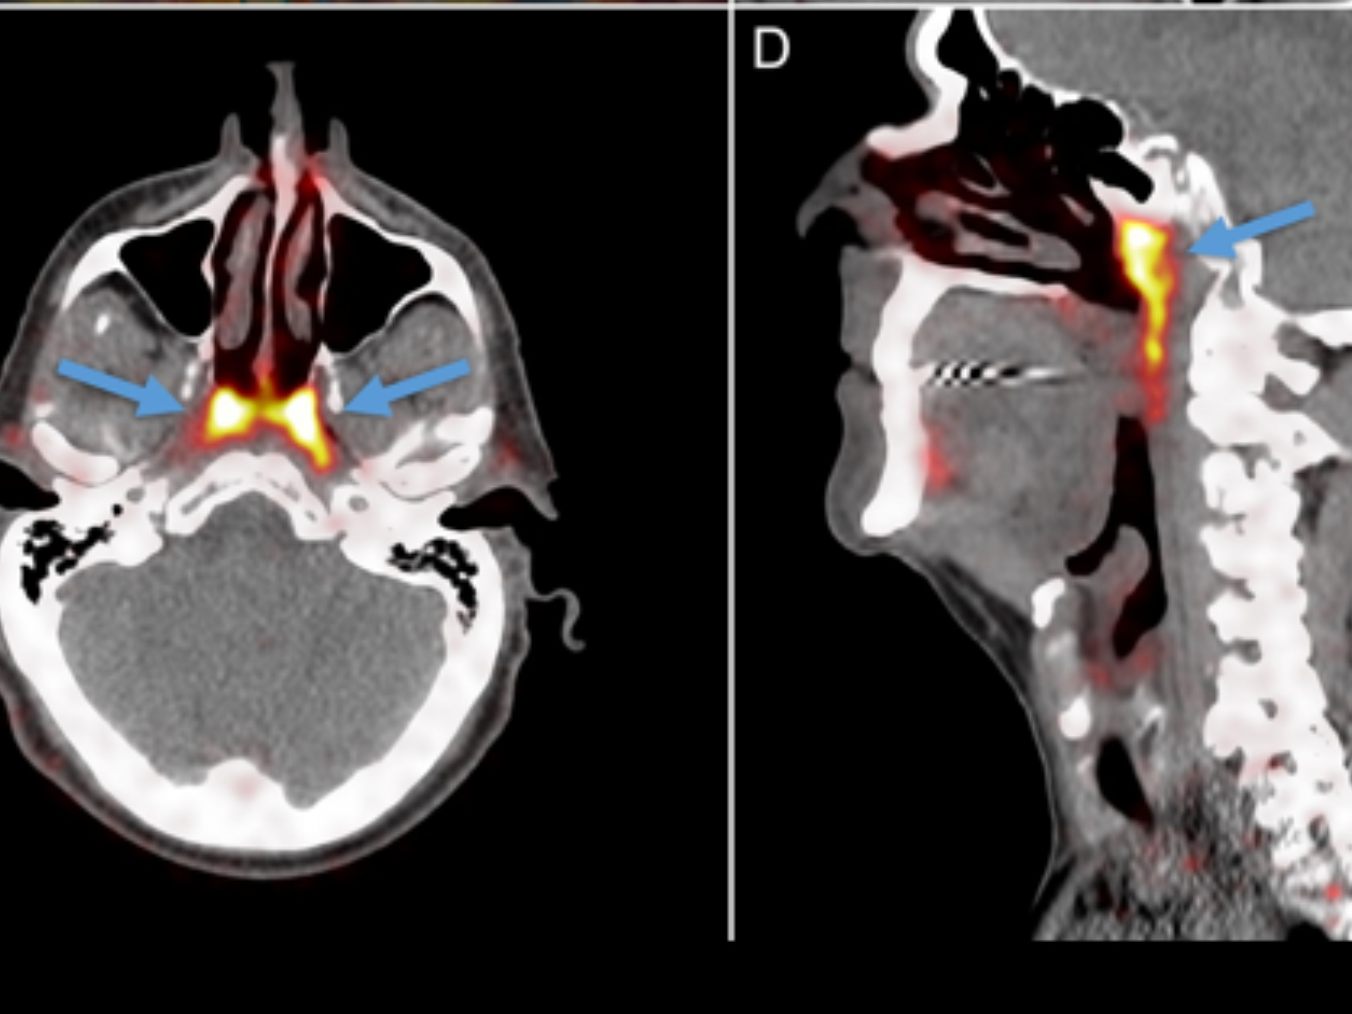

Im Netherlands Cancer Institute führte ein Team von Wissenschaftlern eine Serie von CT- und PET-Scans bei Patienten durch, denen radioaktive Glukose (Zuckerlösung) verabreicht worden war. Der Zweck war, dass der Zucker Tumore auf den Scans sichtbar machen würde, indem er an das Protein PSMA bindet, das in Prostatakrebszellen häufiger vorkommt. Interessanterweise eignet sich das PSMA-Protein auch sehr gut für die Erkennung von Speicheldrüsen. Bei der Analyse der Ergebnisse stellten die Experten fest, dass auch einige Bereiche im Inneren des menschlichen Kopfes aufleuchteten.

Die Tubariusdrüse: Eine bisher unbekannte Speicheldrüse

Im Kopfbereich des menschlichen Körpers befinden sich drei weitere bedeutende Paare von Speicheldrüsen. ©thegreenjournal.com/Radiotherapy and Oncology 2021 154292-298DOI: (10.1016/j.radonc.2020.09.034)